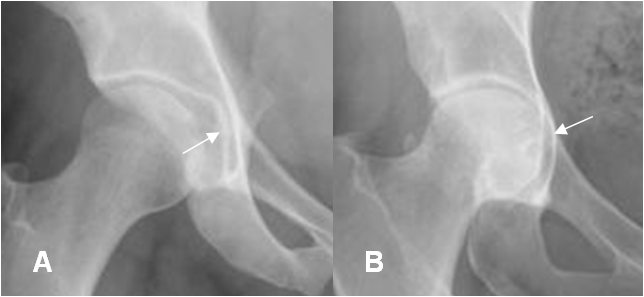

El techo acetabular cruza o es lateral a la línea ilioisquiática. Cuando el borde es medial, se considera una coxa profunda. (4). (Fig 14).

Fig 14. Coxa profunda.

A: Rx AP. Coxa normal. El techo acetabular es lateral, a la línea ilioisquial.

B: Rx AP. Coxa profunda. El techo acetabular es medial, a línea ilioisquial.